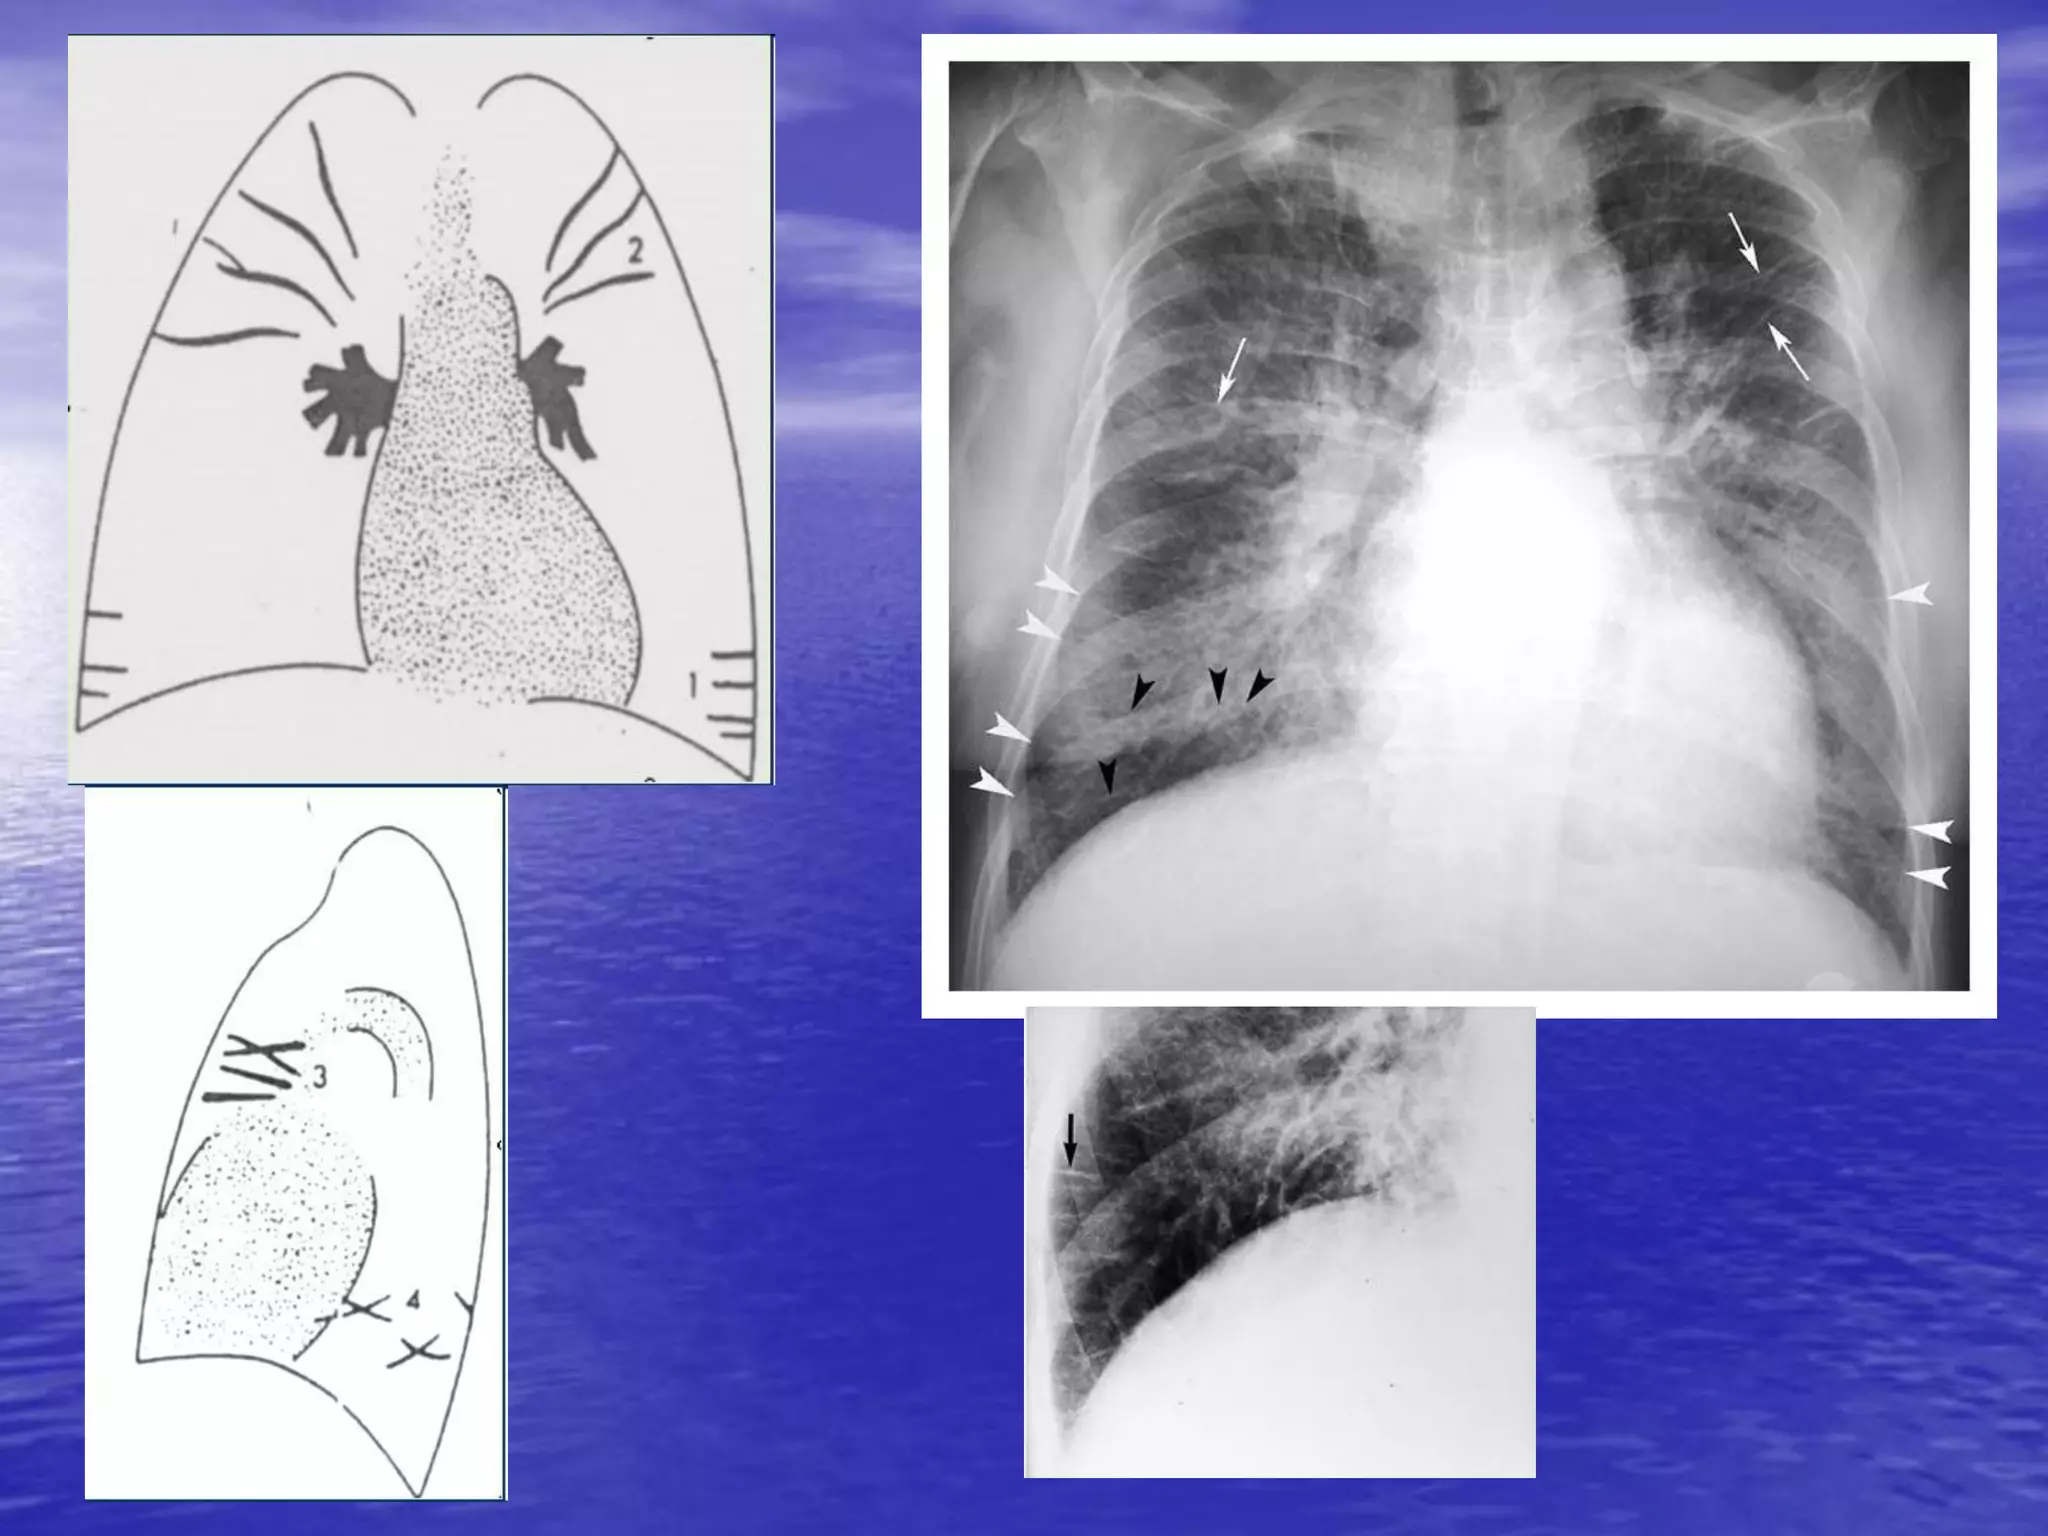

• Tăng tuần hoàn phổi thụ động

– Tăng áp của TM phổi hoặc tăng áp sau mao mạch phổi.

• Kerley A, B, C, D

– Nguyên nhân:

• Hẹp 2 lá, suy tim T, TTP, KPT toàn tiểu thùy

Tuần hoàn phổi/ XQ ngực • Tăng tuần hoàn phổi chủ động – Tăng lưu lượng máu trong ĐMP – tăng tiền mao mạch phổi – Nguyên nhân • Tăng cung lượng tim: sinh lý, bệnh lý • Tim bẩm sinh: tím, không tím • Tăng tuần hoàn phổi thụ động – Tăng áp của TM phổi hoặc tăng áp sau mao mạch phổi. • Kerley A, B, C, D – Nguyên nhân: • Hẹp 2 lá, suy tim T, TTP, KPT toàn tiểu thùy